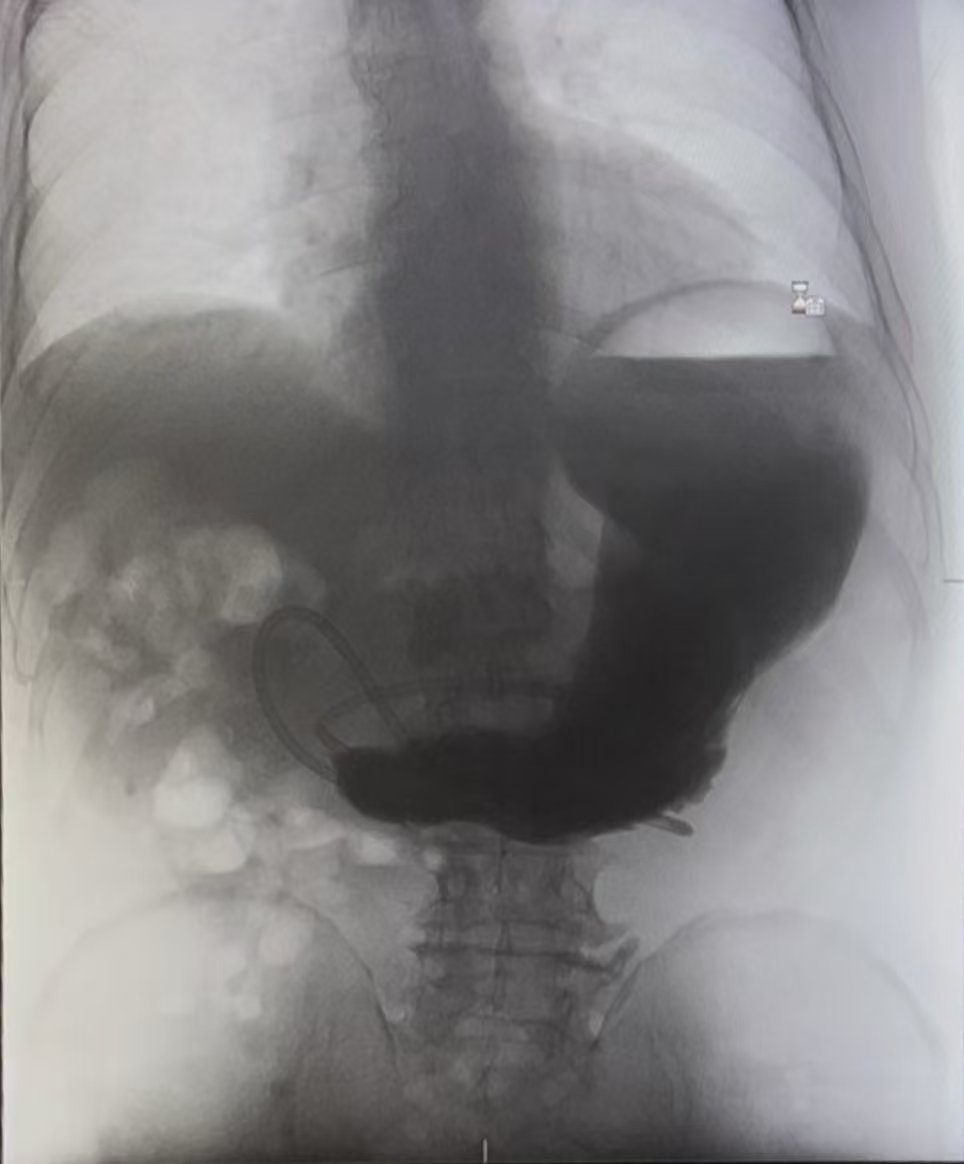

面对疑难病例,医院立即启动多学科会诊(MDT),普通外科(胃肠)联合消化内科、麻醉科、疼痛康复医学科、中医科、心血管内科、骨科、放射科、超声科、临床营养科等多个学科,为患者制定精细诊疗方案。经消化道造影及复查胃镜明确诊断,患者为非甾体抗炎药(NSAIDs)相关胃十二指肠溃疡致十二指肠重度狭窄(最窄处仅容针尖通过),同时继发了肠系膜上动脉综合征及一系列代谢性疾病,治疗难度极大、住院时间长、风险高。

患者肠腔狭窄仅针尖大小(箭头所示),CT亦提示局部结构紊乱不清,基础身体状况较差;无论内镜治疗或外科治疗均存在风险。郑皓医生与患者及家属进行详细病情沟通,患者家属表示积极配合治疗。普通外科(胃肠)及消化内科医疗团队迎难而上,制定个体化救治方案:先后实施2次高风险十二指肠球囊扩张术,配合静脉营养、空肠营养治疗、中医特色治疗,并予以进食后保持俯卧位等护理指导。鉴于患者已行多次CT及消化道造影,主治医师考虑射线辐射等问题,联合超声科为患者行超声造影检查,评估胃动力及胃排空。经过20天昼夜守护,成功规避再喂养综合征、代谢性脑病、误吸等致命并发症,闯过一道道生死关卡。出院时,患者体重较入院时增加3.5kg,胃肠功能完全恢复;出院一周随访,状态持续向好,生活逐步回归正常。三面锦旗,是患者的感恩,更是医者的担当。重庆医科大学附属巴南医院将持续发挥多学科协作优势、精湛诊疗技术与人文关怀,为百姓健康筑牢防线。